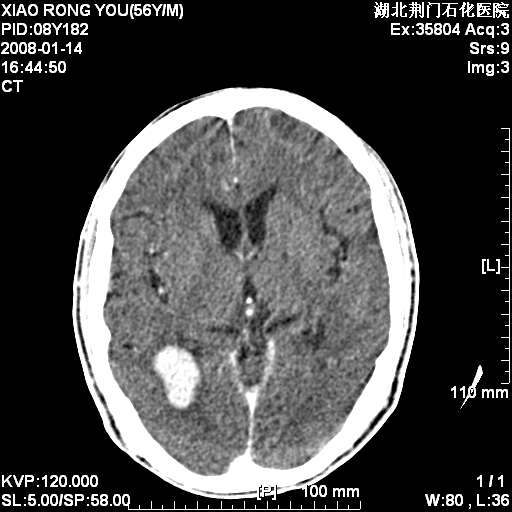

男性,68岁,多年肺结核病史。最近ct复查右肺有占位。

3天后增强

增强明显强化,转移?

如此血管样强化表现,转移瘤不好解释,考虑脑膜瘤或血管瘤

平扫无明显占位及水肿、增强扫描强化明显以血管瘤可能性大